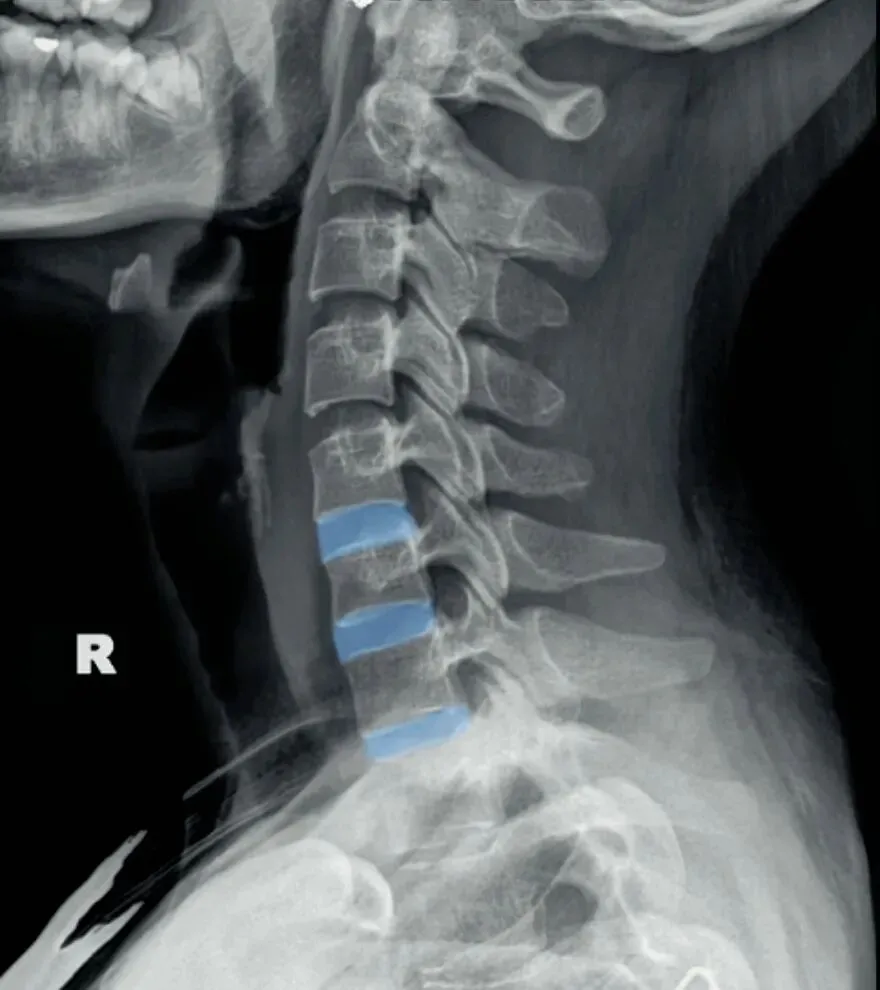

五间是指颈椎椎间隙的变化,主要在颈椎侧位片上观察椎间隙变化同时也反映了椎间盘的变化。

颈椎的退变最早发生在C56椎间盘上,因此C56椎间隙也最早发现变窄的征象。

颈椎骨性椎体为前低后高,

而椎间盘则为前高后低,因此颈椎的生理性前凸是由椎间盘的前高后低所形成的。

在正常情况下,C23、C34和C45间隙大致相等,椎间隙前部为3.8毫米正负0.5毫米,

后缘间隙为1.9毫米正负0.28毫米。

C56间隙较上为宽,而C67间隙最宽,但C7与T1间隙又较窄。